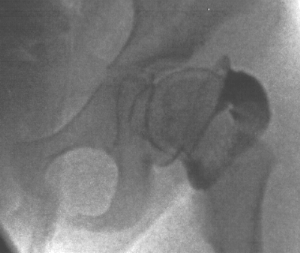

- XRAYS: The pre-operative x-ray demonstrates a seated hip. Intra-operative

arthrogram demonstates dislocation with extreme adduction/flexion.